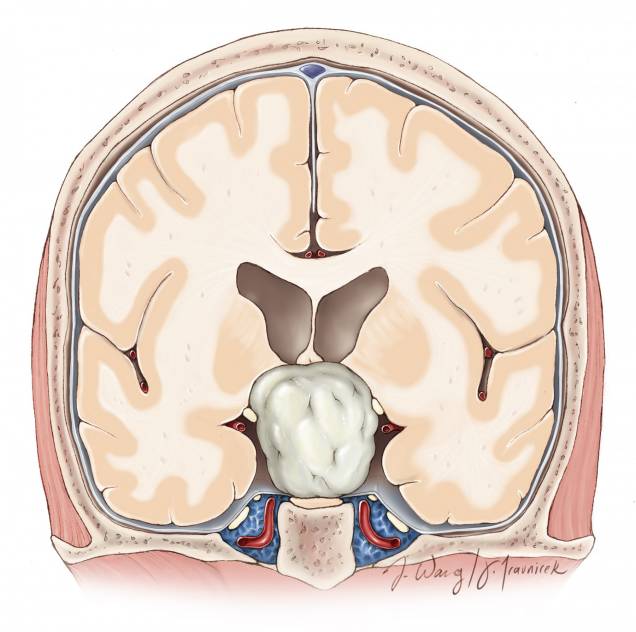

图3. 图示三脑室前部的解剖通道。脑室的大小、因肿瘤所致的室间孔和前脉络裂扩大的程度决定半球间手术通道的侧别。

图7. 图示脉络丛、透明隔静脉和丘纹静脉的手术解剖。通过脉络膜裂前部一小段分离扩大室间孔的关键操作是在隔静脉汇入丘纹静脉之前切断。穹隆和丘纹静脉必须被保留。尽管笔者更愿意沿丘脑侧分离脉络裂而不是沿穹隆一侧分离来达到保护穹隆的目的,但是脉络裂的实际解剖更可能提示最合理的分离界面。换句话来讲,笔者并不推荐固定的分离策略(总是沿着丘脑脉络带或者穹隆带)。穹隆构成室间孔前壁的边界,在器械移动过程中应该注意保护。